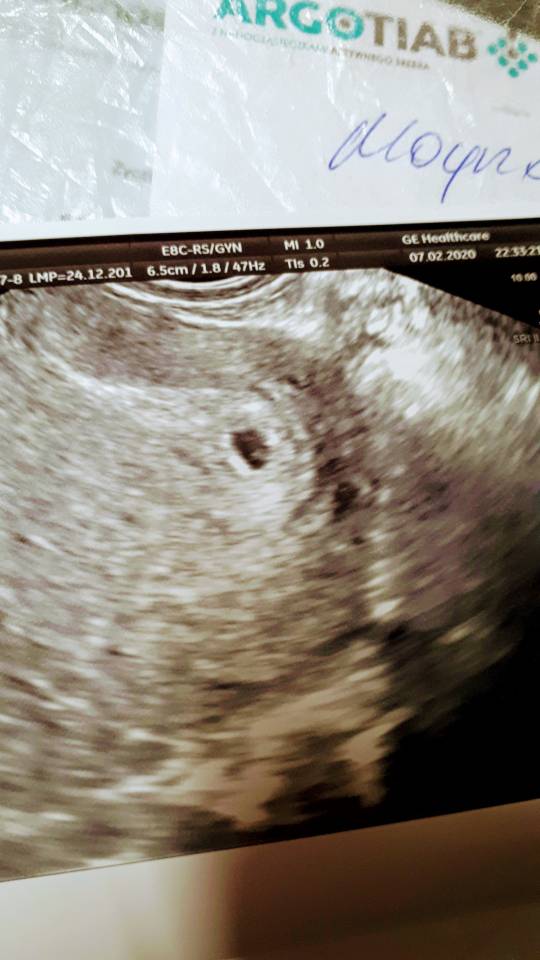

Przyjaciółka do mnie ze ona widzi 2 pęcherzyk na usg[emoji33][emoji2957][emoji2957][emoji2957][emoji2957]

USER_SCOPED_TEMP_DATA_MSGR_PHOTO_FOR_UPLOAD_1581103888760~2.jpeg